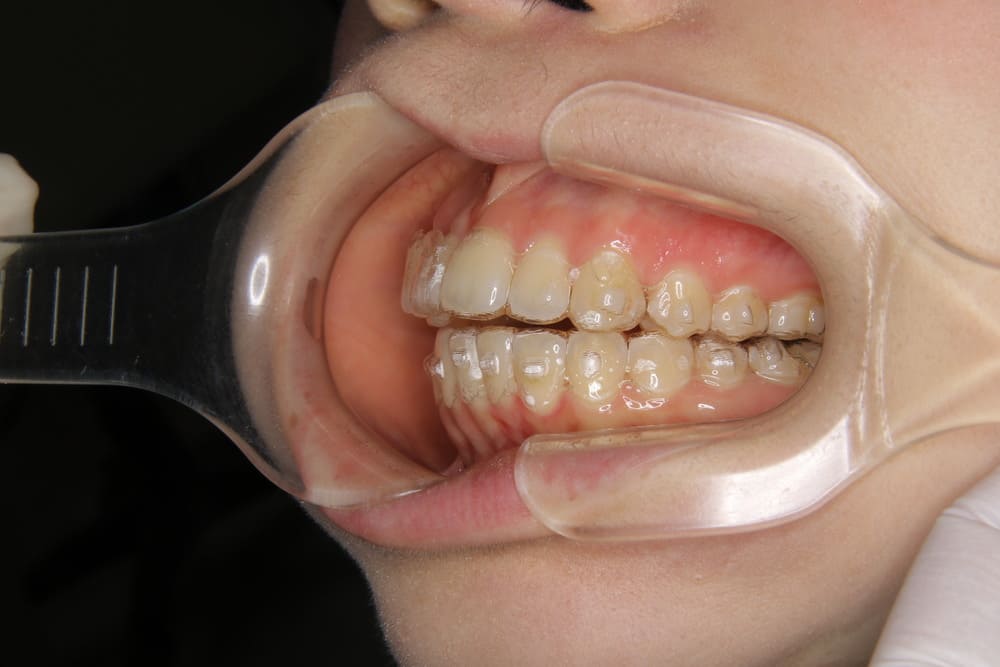

取り外しのできるマウスピース型の矯正歯科治療です。

透明のマウスピースで目立たず、痛みもない矯正装置を使用します。

2精密検査

レントゲン撮影、口腔内写真・顔貌の写真撮影、口腔内スキャナー(iTeroなど)による精密な歯型採得など、治療計画の立案に必要なデータを収集します。